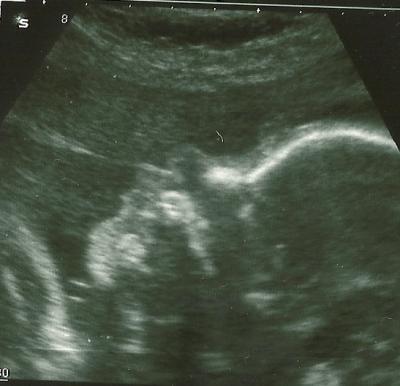

hatte heute VU und unser kleiner Noah wiegt schon 1600 g , ist alles i.O. meinte der FA. Aber CTG ist ja immer furchtbar find ich, dass muss meinen ja so stören, dann drücken die mit dem ollen Plättchen immer in Bauch um den Herzschlag gut aufzeichnen zu können, war alles rot hinterher und hat bischen geschmerzt. Aber hauptsache der Kleine ist gesund.

schönes US-Bild vom Profil des kleinen so eins will ich auch, ich glaub ich muss mal mit meinem FA schimpfen. Naja hab ja bald 3. Screening

Wirklich ein tolles Profilbild !